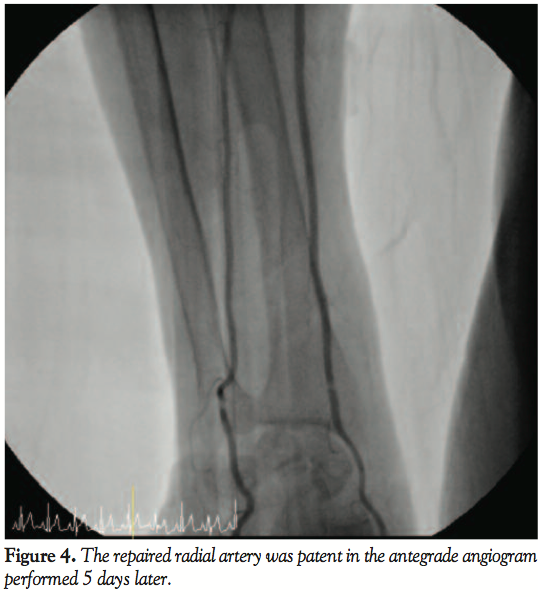

local anesthesia in the catheterization laboratory, a vascular surgeon incised the skin, cut down the radial artery, retrieved the distorted stent successfully, and repaired the radial artery. Five days later, the proximal LAD lesion was treated successfully with stent through the right femoral artery and the repaired radial artery was patent in the antegrade angiogram (Figure 4). The patient was discharged 2 days later with an improvement of anginal symptom and no complication in the arm and hand (Figure 5).